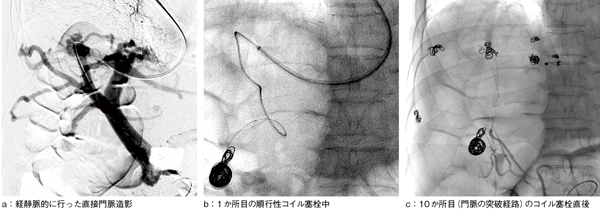

左鎖骨窩静脈から穿刺し,中肝静脈-門脈右枝へカテーテルを突破することに成功し,直接門脈造影にて両葉に多発する門脈肝静脈短絡を確認した(図3 a)。順行性にマイクロカテーテルを進め,可能なかぎり短絡から門脈末梢の9か所にコイルを留置し(図3 b),門脈への突破経路も塞栓して手技を終了した(図3 c)。血管塞栓術前は血中アンモニアが190μg/dL台と高値であったが,約1週間後には50mg/dL台まで低下した。ほぼ同時期にMRA再検し,右葉を中心に門脈・肝静脈の末梢描出減弱および中枢細径化を確認した(図4)。

図3 経静脈的に行った直接門脈造影および血管塞栓